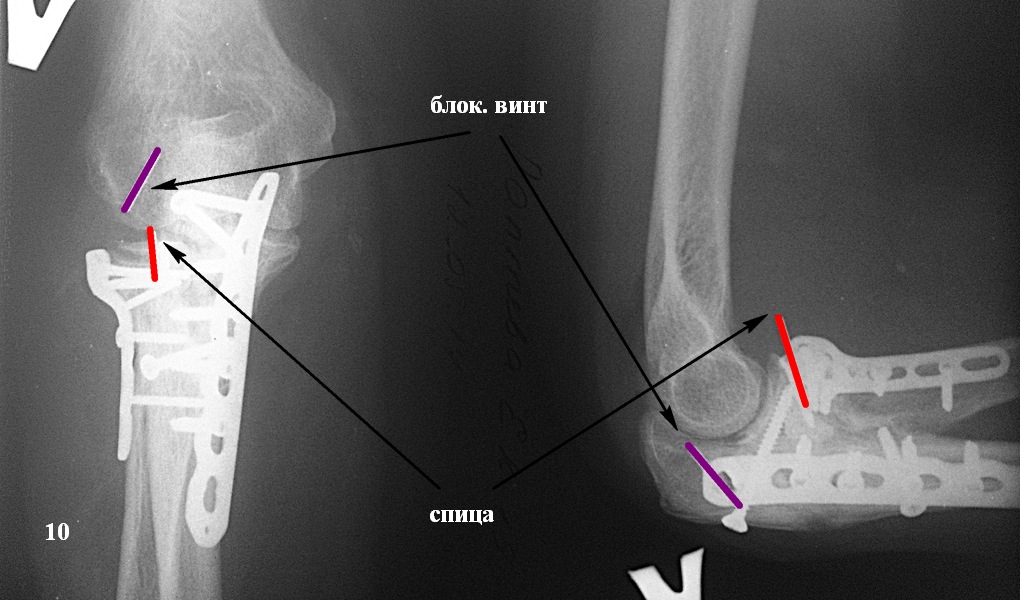

Казалось бы все счастливы, но в середине мая этого года (6 месяцев после операции) со слов больной: "Сидела на кресле, ничего не делала. И тут "щелк" в локте, с болью и легким хрустом при ротации предплечья". На снимке (рис. 10) перелом блок. винта из пластины на головке луча и миграция оставленной спицы. Скиаграмма для наглядности (рис. 11). Посоветовали ограничить движения, обезболивание. и сделать контроль через 3 недели.